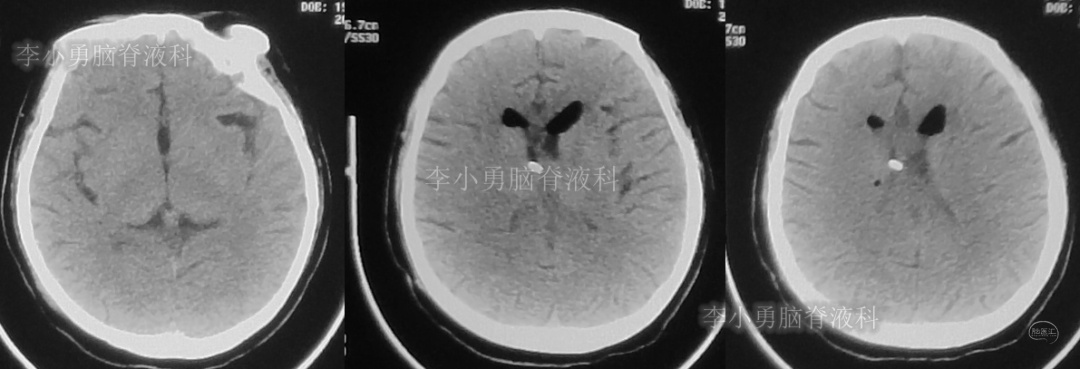

次日,即2018年11月11日,患者第2次到给予脑室腹腔分流术的医院,复查头颅CT(图-5)见脑积水仍严重。

图-5:2018年11月11日头颅CT

但第2次调压后2周,即2018年11月28日,再次到当地的第1家医院复查头颅CT(图-6)见脑积水缓解。

图-6:2018年11月28日头颅CT